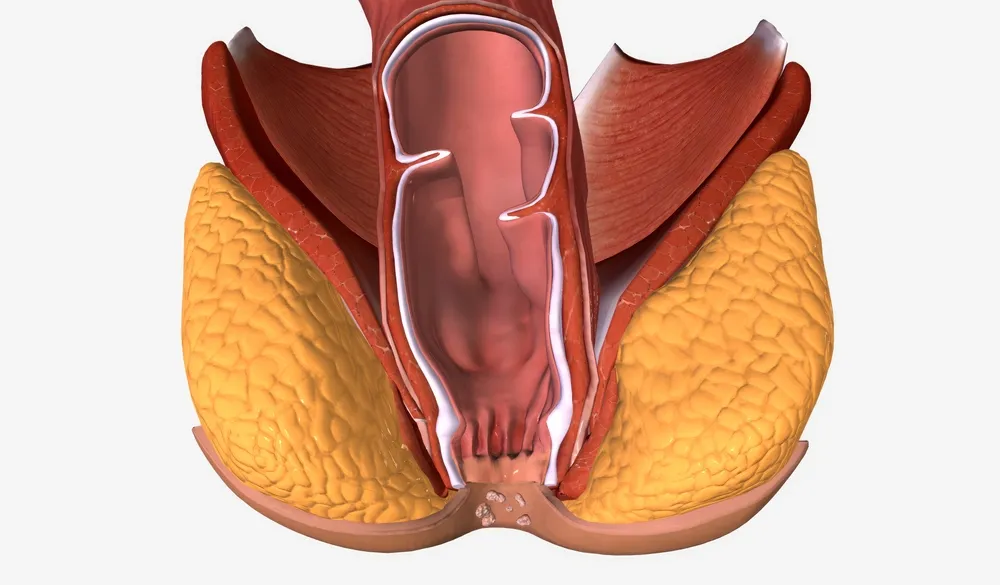

۱. بواسیر یا هموروئید

بواسیر یکی از شایعترین اختلالات نشیمنگاهی است که در نتیجه التهاب و گشاد شدگی عروق وریدی در کانال مقعد ایجاد میشود. هموروئید ممکن است داخلی یا خارجی باشد و علائمی مانند خونریزی هنگام دفع، درد، خارش و احساس توده در مقعد ایجاد کند.

معرفی کامل بیماری بواسیر یا هموروئید با علائم و درمانهای مؤثر

بواسیر یا هموروئید (Hemorrhoids) یکی از شایعترین بیماریهای ناحیه مقعد و دستگاه گوارش انتهایی محسوب میشود که میلیونها نفر در سراسر جهان را درگیر کرده است. این بیماری در نتیجه تورم، التهاب یا گشاد شدگی غیرطبیعی عروق وریدی در ناحیه کانال مقعد ایجاد میشود و میتواند با علائمی چون درد، خونریزی، خارش، سوزش و احساس توده همراه باشد.

انواع بواسیر و تفاوت آنها

بواسیر بهطور کلی بر اساس محل قرارگیری عروق متورم و علائم بالینی به دو نوع اصلی تقسیم میشود:

۱. بواسیر داخلی (Internal Hemorrhoids)

این نوع از بواسیر در داخل کانال آنال، بالاتر از خط دندانهای (dentate line) قرار دارد و معمولاً در مراحل اولیه بدون درد است، اما میتواند با خونریزی روشن هنگام دفع همراه باشد. در برخی موارد، این نوع بواسیر از مقعد خارج میشود که اصطلاحاً به آن «پرولاپس هموروئید» گفته میشود.

۲. بواسیر خارجی (External Hemorrhoids)

این نوع از بواسیر در زیر خط دندانهای، یعنی در ناحیه خارجی مقعد ایجاد میشود و اغلب با درد، التهاب و گاهی لخته شدن خون (ترومبوزه) همراه است. بواسیر خارجی ممکن است به شکل یک توده سفت و دردناک در نزدیکی مقعد ظاهر شود و حتی بدون خونریزی نیز ناراحتی زیادی برای فرد ایجاد کند.